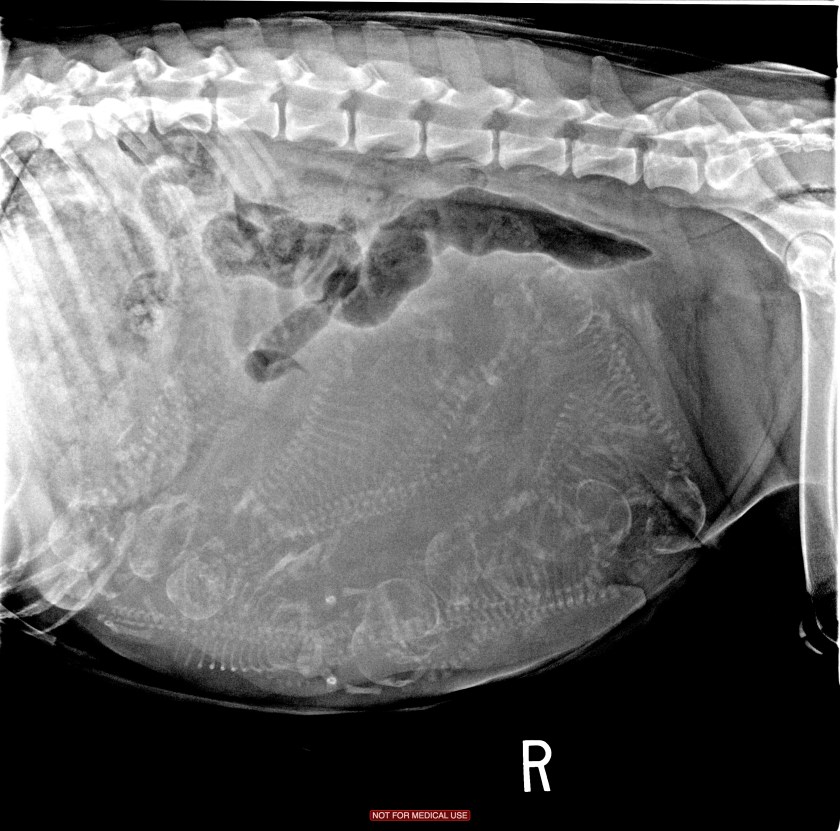

Okay, folks… I’ve been going over and over this x-ray. The goal is to match up skulls and spines (that also have ribs) to get an accurate puppy count.

I went in predicting 10 puppies and that is what the vet confirmed with this x-ray! Why ten? Because Deja has the length to hold puppies and she is “overhanging quite a bit! She is enormous! Weighing in today at 69.5 pounds!